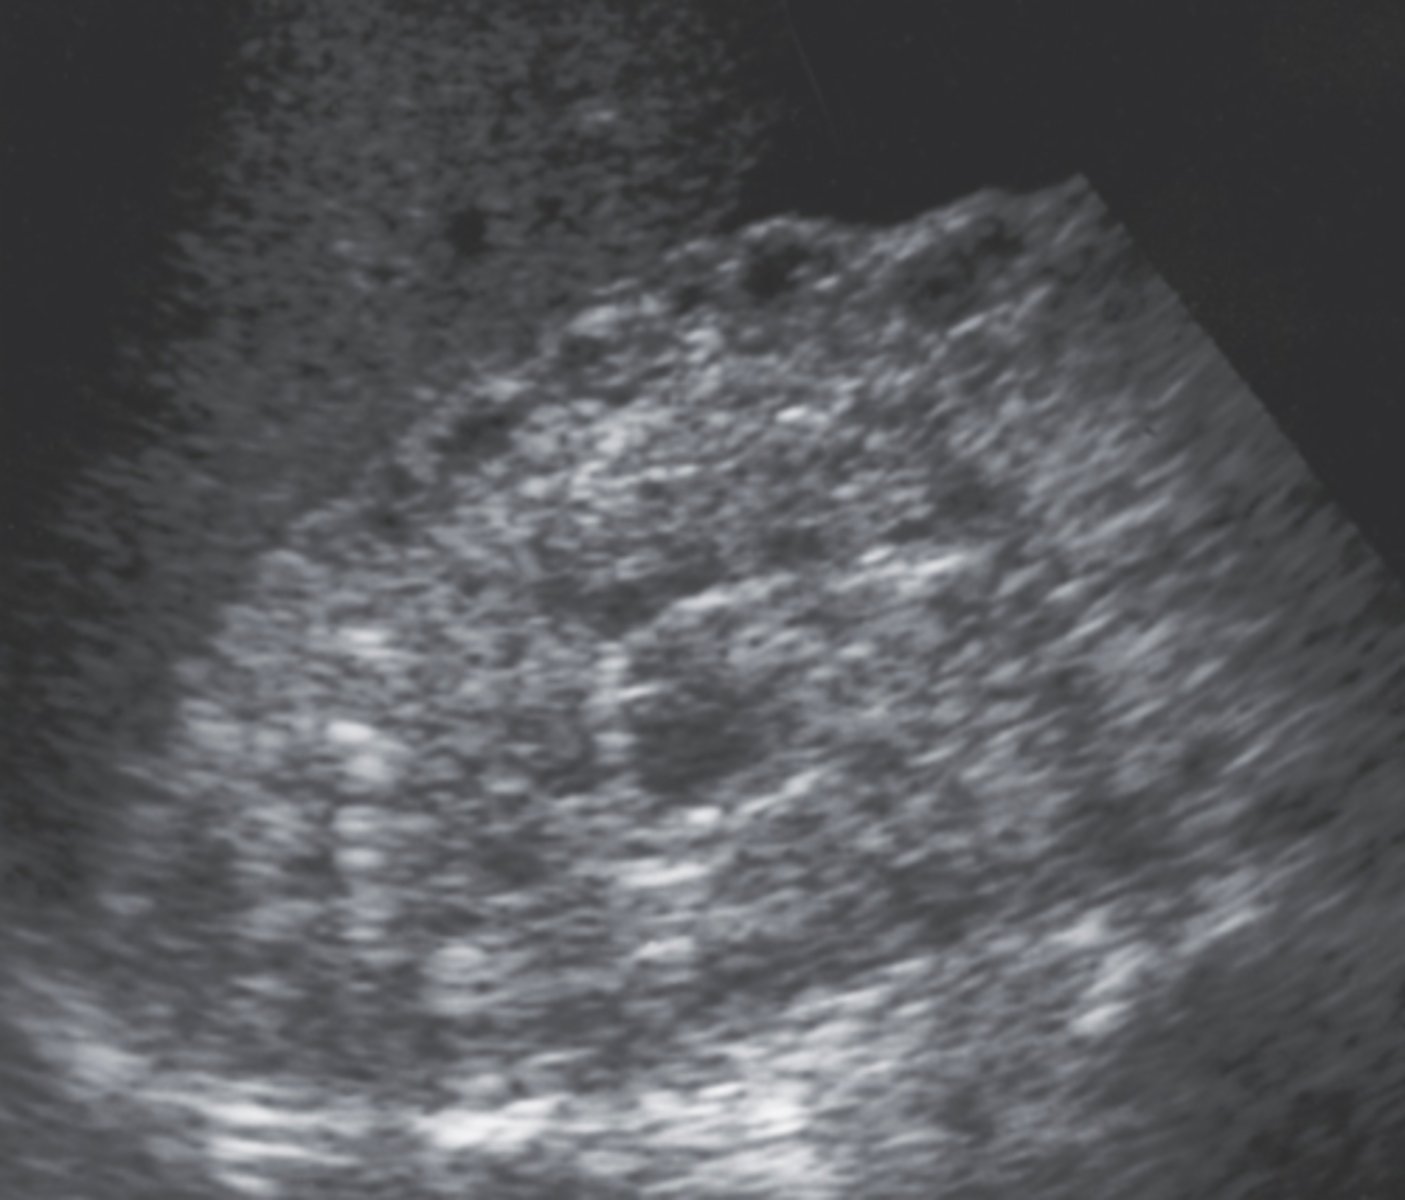

1. The sonographic finding in Figure 7-40 is most consistent with what diagnosis?

a. ARF

b. CRF

2. What is the most common cause of the disorder noted in Figure 7-40?

a. Diabetes mellitus

35. Which of the following is the most common cause of CRF?

a. Hypertension

b. Diabetes mellitus

37. Sonographically, compared to normal kidneys, those affected by CRF will appear:

a. normal in size with a decreased echogenicity

d. smaller in size and more echogenic